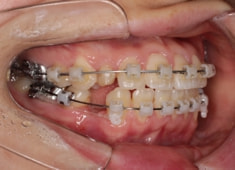

治療中